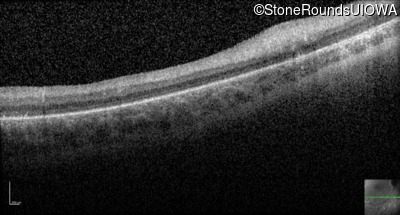

Optical Coherence Tomography - Right -

No Light Perception

Exemplar

Expanded OCT Stack

×